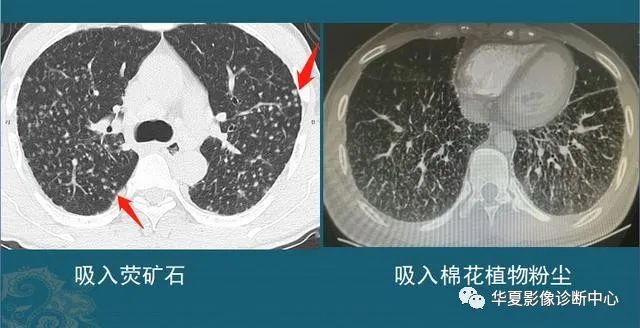

下图左边是一个炎症性结节,右图是结核球,都是形态不规则,边缘有毛刺,伴有胸膜牵拉:

这种结节有时单纯从CT片的形态分析,跟肺癌鉴别困难,需要抗炎治疗后复查,或者增强CT看结节的强化特点,炎症结节常常明显均匀强化,结核球一般不强化或者环形包膜样强化(肺结核会破坏内部组织包括血管,引起广泛坏死),肺癌多为轻中度不均匀强化(肿瘤血管少而乱)。

还有些无法确诊的,需要多学科会诊,借助正电子发射计算机断层显像(PET-CT)或者穿刺,或者手术后病理等手段。